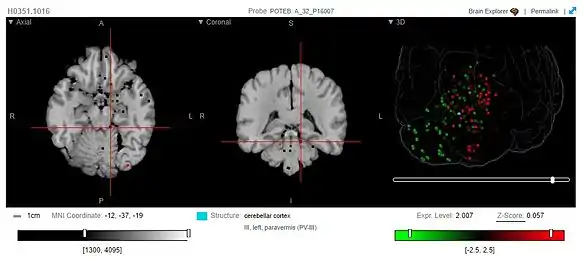

Some studies have used POTEB probes to study the expression of POTEB in the human brain. However, the only region with notable POTEB expression is the cerebellar cortex, responsible for motor function and some cognitive functions.[14]